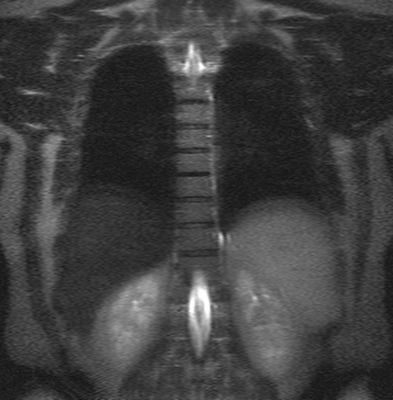

Рентген дает снимок, выполненный только в 2 направлениях (в прямой и боковой проекциях). Но при необходимости могут использоваться специальные укладки. МР-томограф делает множество послойных снимков в трех плоскостях, расположенных перпендикулярно по отношению друг к другу.

Множественные (2) гемангиомы на МРТ грудного отдела позвоночника

При получении результатов МРТ рентгенолог имеет доступ к изображениям любого отрезка исследуемой области. Можно рассмотреть каждую связку или спинномозговой корешок, в том числе в разрезе. Цифровые технологии упрощают работу со снимками для врача. При необходимости доктор может изучить один и тот же отрезок с разных ракурсов, увеличить или уменьшить картинку.

Грудной отдел позвоночника на МРТ в коронарной проекции